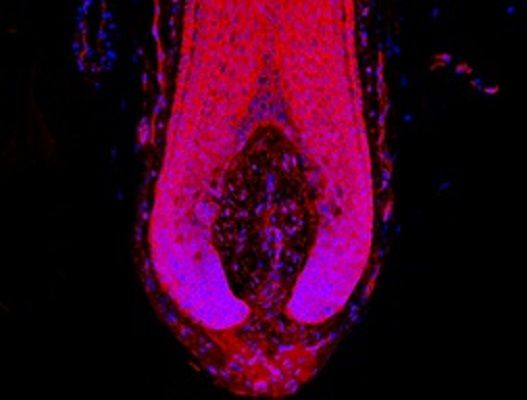

Obraz

© University of Manchester

W ten sposób Brytyjczycy natrafili na związek WAY-316606. Najlepiej stosować go zewnętrznie, dlatego niewykluczone, że wkrótce powstaną szampony zawierające substancję przeciw łysieniu.

Dzięki współpracy z chirurgiem przeszczepu włosów, dr Asimem Shahmalakiem, mogliśmy przeprowadzić eksperymenty z mieszkami włosowymi, które zostały hojnie oddane przez ponad 40 pacjentów - powiedział dr Nathan Hawkshaw.